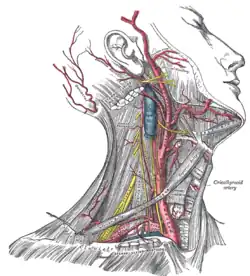

The common carotid artery is contained in a sheath known as the carotid sheath, which is derived from the deep cervical fascia and encloses also the internal jugular vein and vagus nerve, the vein lying lateral to the artery, and the nerve between the artery and vein, on a plane posterior to both. On opening the sheath, each of these three structures is seen to have a separate fibrous cover.

At the lower part of the neck, the common carotid artery is very deeply seated, being covered by the integument, superficial fascia, the platysma muscle, deep cervical fascia, the sternocleidomastoid muscle, the sternohyoid, sternothyroid, and the omohyoid; in the upper part of its course it is more superficial, being covered merely by the integument, the superficial fascia, the platysma, deep cervical fascia, and medial margin of the sternocleidomastoid.

When the sternocleidomastoid muscle is drawn backward, the artery is seen to be contained in a triangular space known as the carotid triangle. This space is bounded behind by the sternocleidomastoid, above by the stylohyoid and the posterior belly of the digastric muscle, and below by the superior belly of the omohyoid.

This part of the artery is crossed obliquely, from its medial to its lateral side, by the sternocleidomastoid branch of the superior thyroid artery; it is also crossed by the superior and middle thyroid veins (which end in the internal jugular vein); descending in front of its sheath is the descending branch of the hypoglossal nerve, this filament being joined by one or two branches from the cervical nerves, which cross the vessel obliquely.

Behind, the artery is separated from the transverse processes of the cervical vertebrae by the longus colli and longus capitis muscles, the sympathetic trunk being interposed between it and the muscles. The inferior thyroid artery crosses behind the lower part of the vessel.

Medially, it is in relation with the esophagus, trachea, and thyroid gland (which overlaps it), the inferior thyroid artery and recurrent laryngeal nerve being interposed; higher up, with the larynx and pharynx. Lateral to the artery, inside the carotid sheath with the common carotid, are the internal jugular vein and vagus nerve.

At the lower part of the neck, on the right side of the body, the right recurrent laryngeal nerve crosses obliquely behind the artery; the right internal jugular vein diverges from the artery. On the left side, however, the left internal jugular vein approaches and often overlaps the lower part of the artery.

Behind the angle of bifurcation of the common carotid artery is a reddish-brown oval body known as the carotid body. It is similar in structure to the coccygeal body which is situated on the median sacral artery.